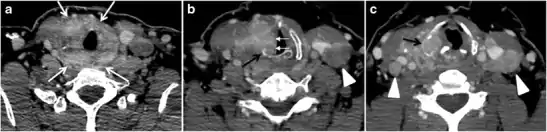

Fig. 6. A 61-year-old female patient with locally aggressive PTC. an Enhanced axial CT scan of the neck demonstrates a heterogeneous infiltrative thyroid mass. This mass diffusely involves the entire gland and circumferentially encases the trachea with involvement of bilateral tracheoesophageal grooves (white arrows). b, c Additional axial cranial images show right cricoid cartilage destruction (black arrows in b), right thyroid cartilage destruction (black arrow in c), right vocal cord paralysis (white arrows in b), and bilateral cervical lymphadenopathy (arrowheads).[1]